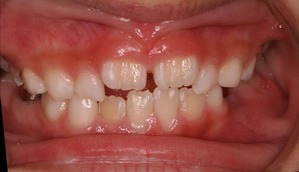

初診時はひどい状況でした。

まず、歯列矯正治療以前に虫歯の管理がまったくされておりませんでした。

最近の東京都内ではこのようなお子様は数が少なくなってきたと思います。

年齢は7歳 小学校2年生ですので、 本来なら上下前歯が大人の歯に生えそろい、横の部分は乳歯がすべてある状況です。 いわゆる生えかわりの安定期という時期ですが、この患者さんはすでに何本か乳歯を抜いてしまっております。

また、下の前歯の歯肉も下がってきており、グループ的には1に属するものの、この悲惨は口腔内環境下では、矯正治療をおこなっても散々な結果になることが予想されました。